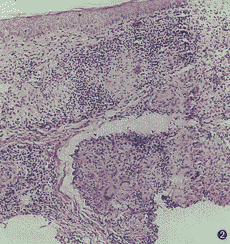

尋常狼瘡尋常狼瘡的病理變化主要發生在真皮的淺層,但亦有蔓延到真皮深層甚至皮下組織者,並可導致皮膚附屬器破壞。

病理浸潤主要為結核樣結節,並很少見有乾酪樣壞死形成的結節,即使有亦很輕微。浸潤細胞主要為淋巴細胞、上皮樣細胞和巨細胞,巨細胞雖然通常是核呈邊緣排列的郎罕巨細胞形,但有些是核呈不規則排列的多核巨細胞。損害越早,淋巴細胞浸潤越多,圍繞在浸潤灶周圍。損害較久時則上皮樣細胞及郎罕巨細胞占優勢,上皮樣細胞大都呈同心圓形集簇或不規則排列。浸潤灶內無血管,其中膠原纖維變性,最後彈力纖維亦可變性破壞。病灶癒合時,邊緣部網狀纖維緻密和膠原化,有廣泛纖維組織增殖。彈力纖維不能恢復。表皮變化為繼發性的,在有些病例中可有棘層肥厚、角化過度或乳頭.

瘤樣增生,甚至假上皮瘤樣增生,偶或發生鱗狀細胞癌。但有些病例,可因真皮內的浸潤壓迫而使表皮萎縮變薄,甚至破壞形成潰瘍,並可因繼發感染而化膿,以致在浸潤中發現許多中性粒細胞、嗜酸性粒細胞及其它化膿性細菌。在尋常狼瘡的病理組織中,雖然可有結核桿菌的存在,但不易被發現,甚至培養和動物接種亦不能經常成功。